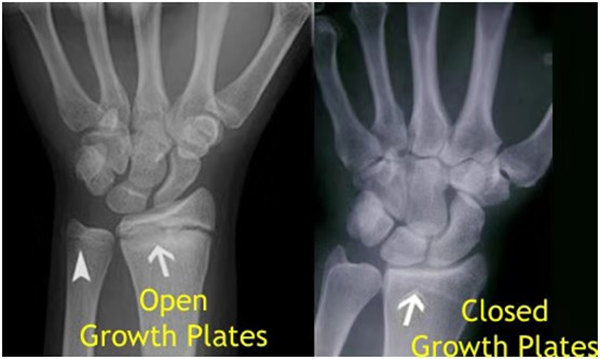

其實(shí)想要了解孩子的生長(zhǎng)發(fā)育情況或者說孩子未來身高的趨勢(shì),測(cè)骨齡是個(gè)好辦法。臨床上通常拍攝兒童的左手正位X光片 , 采用《中華-05》骨齡標(biāo)準(zhǔn)對(duì)手腕骨發(fā)育程度進(jìn)行骨齡評(píng)價(jià)。

我們都知道,人體的高矮是由骨骼的生長(zhǎng)發(fā)育決定的,特別是下肢長(zhǎng)骨。長(zhǎng)骨呈長(zhǎng)管狀,在長(zhǎng)骨的兩端有一種專管骨骼生長(zhǎng)的骺軟骨,它與干骺端之間有一盤狀軟骨結(jié)構(gòu)稱為骺板(線),在幼兒的X光片上表現(xiàn)為一條較寬的透光帶。 (見下圖)

未成年時(shí)隨著年齡的增加骺軟骨端不斷骨化,骨骼就不斷增長(zhǎng)。當(dāng)骨骺線完全閉合時(shí)骨骼就停止生長(zhǎng),個(gè)子也就不再增長(zhǎng)了。一般骨骺端完全閉合的年齡是18~20歲左右。